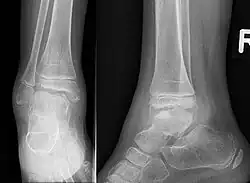

| Trevor disease in a nine-year-old girl: talus | |